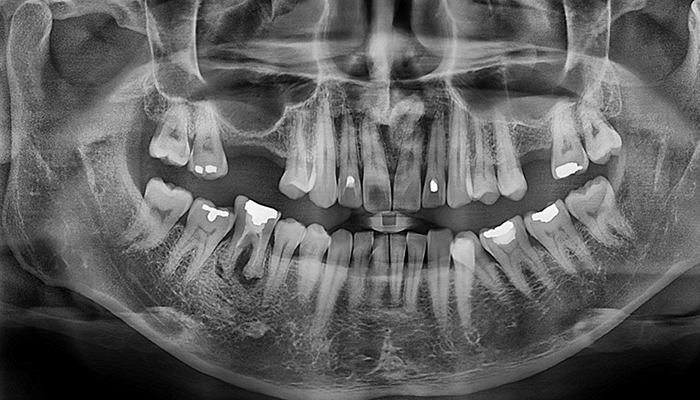

임플란트 수술시, 상악동과 잇몸뼈 사이에 뼈가 남아 있지 않았을 때 상악동막을 들어올리고 빈 공간에 뼈를 이식하여 임플란트 식립을 위한 공간을 확보하는 수술을 상악동 거상술이라 합니다.

밀도가 높고 두꺼운 턱뼈가 구성된 아래턱과는 달리 위턱은 얇은 뼈 위에 코와 광대 사이 빈 공간에 식립해야 하는 고난도 수술로 임플란트 수술 경험이 많은 의료진에게 받는 것이 중요합니다.

치아를 빼고 오래 방치하거나 치아를 잡고 있는 치조골이 많이 녹은상태에서 치아를 빼면 위쪽 턱뼈가 부족할 수 있습니다.